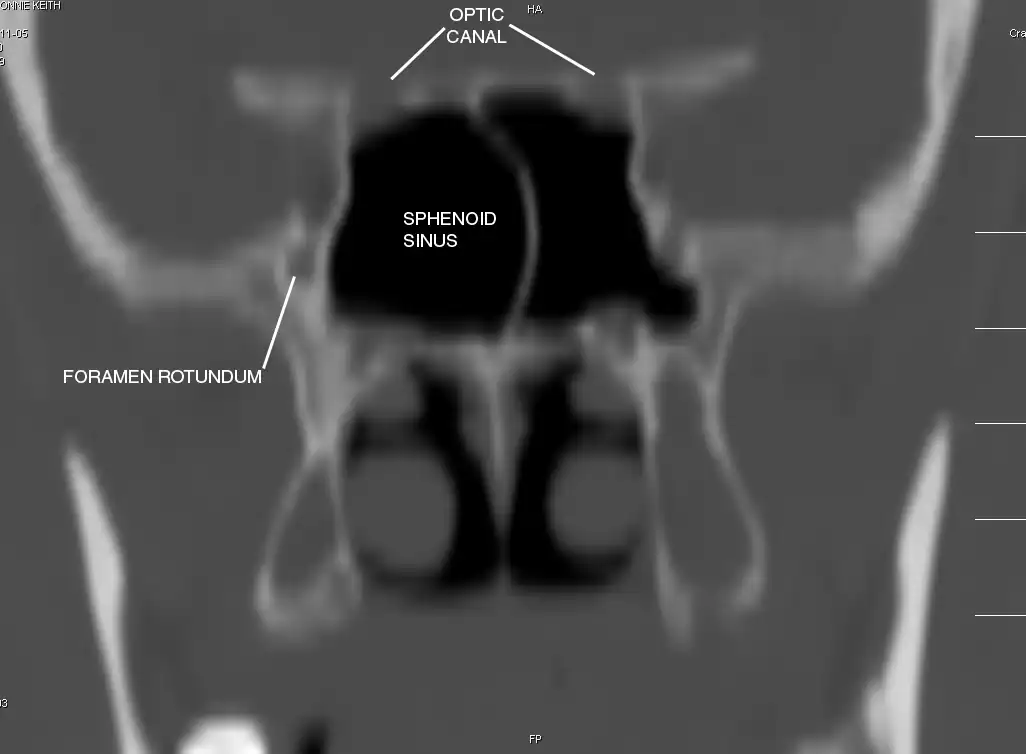

Sphenoid Sinus has 12 close structures: II, III, IV, V1, V2, VI, Vidian Nerve, Carotid artery, Brain, Dura, Pituitary.

Pertinent Sinonasal Anatomy

II = Optic Nerve: 25-50% with bony dehiscence into sphenoid sinus.

V2 = Maxillary division, Trigeminal Nerve: exits foramen rotundum, superomedial to V3's foramen ovale.

C = Carotid Artery: often with bony dehiscence into sphenoid. Together with CN II forms opticocarotid recess.